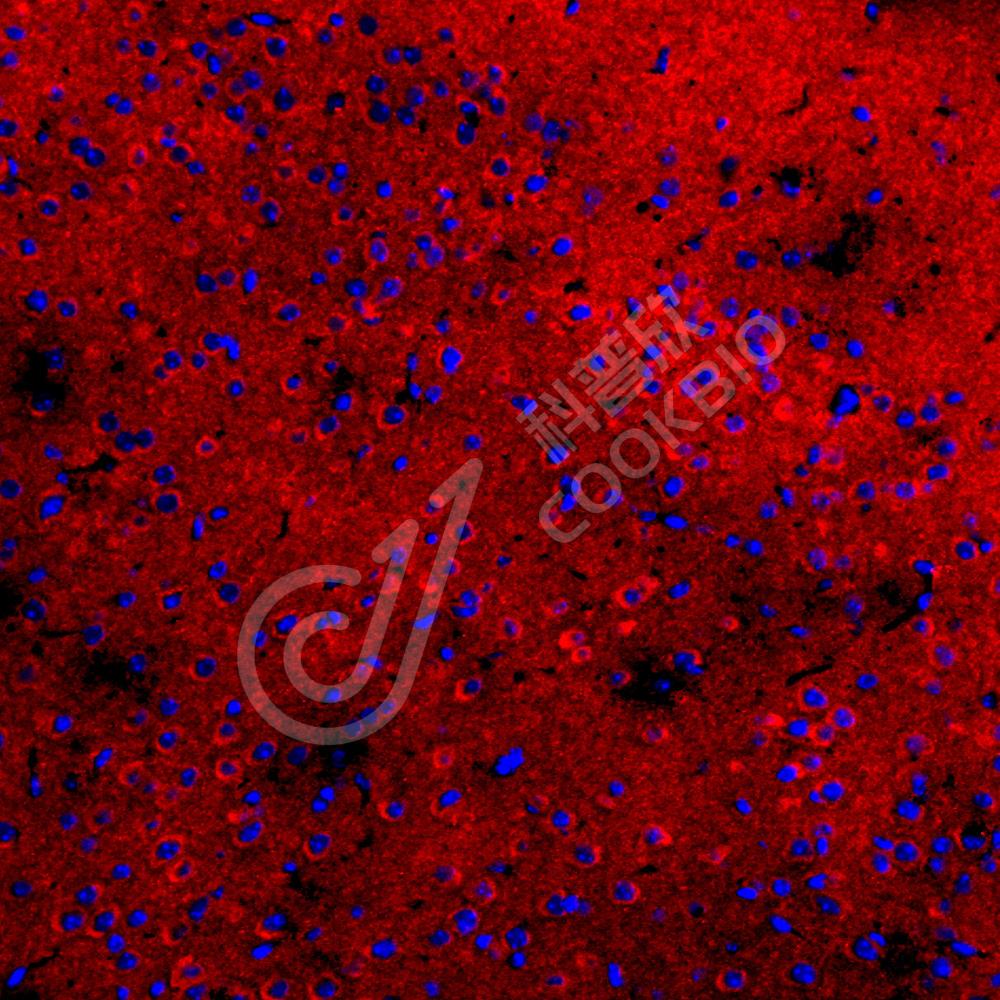

IF检测Tau蛋白(货号 K1334827)(红色).

样品: 小鼠脑, 4%多聚甲醛 (货号KSG1101) 固定12-24小时.

抗原修复: Tris-EDTA抗原修复液(pH 9.0) (KSG1203), 98℃, 20分钟.

封闭: 3% BSA(货号KSGC305010)的PBS溶液, 室温孵育30分钟.

—抗: 1: 1500稀释, 4℃ 孵育过夜.

二抗: Cy3标记山羊抗兔IgG (H+L) (货号KB63909), 1: 300稀释, 室温孵育1小时.